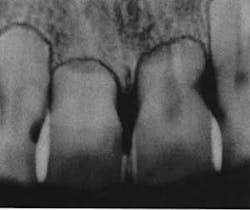

Before you begin treatment, take records. These include photos, x-rays, and diagnostic models. It is important to document the state of the patient prior to treatment. Regarding root resorption, it is essential to take radiographs. Any orthodontic treatment should include pretreatment and post-treatment radiographs that allow visualization of the roots. I recommend panoramic radiographs for this purpose. While it is common in general dentistry to take panoramic x-rays every five years, this is too long for patients in orthodontic treatment. Root resorption can be evident radiographically in as little as six months of orthodontic treatment. Because of this, I take panoramic x-rays every six to eight months in my practice.